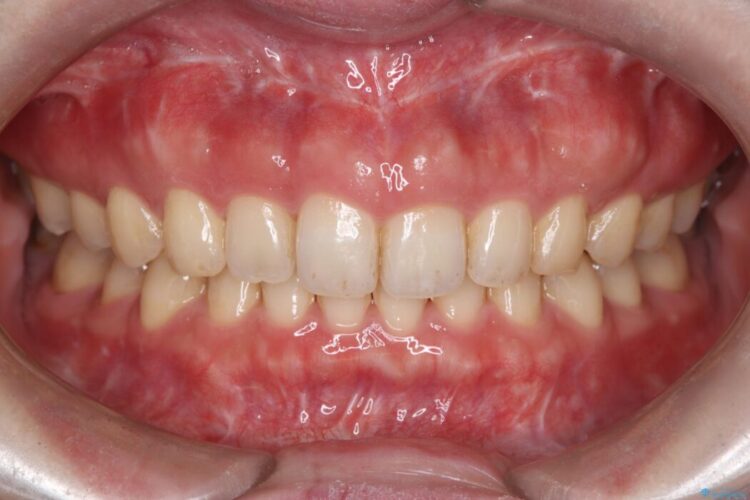

切らない・腫れにくい短期間治療【1DAYインプラント】

右上の奥歯に根尖病変があり、長期的に安定した治療をご希望されたため、インプラント治療を行いました。

治療期間(治療回数):3ヶ月(2~5回) | 概算治療費:638,000円(税込)